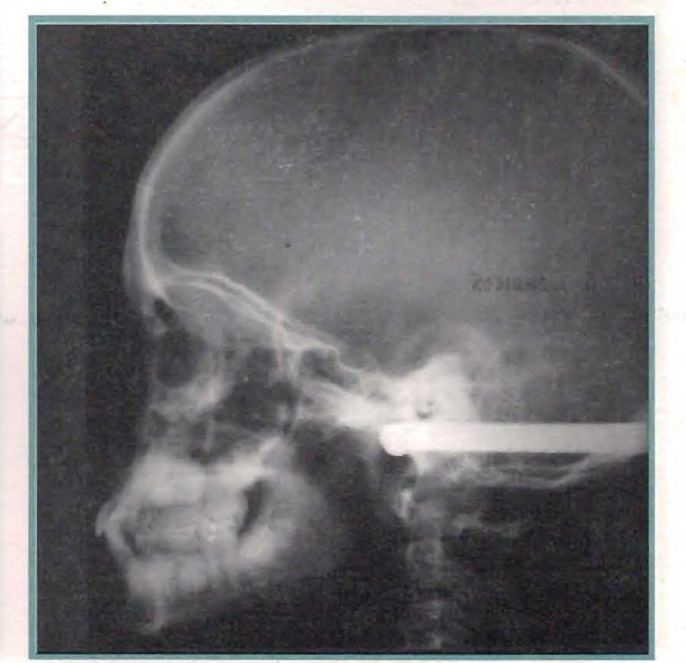

Cintya chega ao curso a partir da consulta privada de um colega, que a trouxe preocupado com a gravidade do caso.

A análise facial apresenta os sinais clássicos das mesiorrelações.

Na inspeção clínica, apresenta um verdadeiro colapso, tanto transversal quanto anteroposterior do maxilar superior, com um degrau anterior de 4 mm, e mordida cruzada bilateral posterior.

O estudo cefalométrico mostra um déficit de 5° na posição do maxilar superior em relação à base do crânio, embora também observemos uma diminuição de 3,5 mm no tamanho. Claro, a posição do maxilar inferior está adiantada, mas felizmente seu tamanho é menor do que o esperado.

A magnitude dos déficits dos diâmetros transversais, e a característica dos eixos dentários, paralelos às bases ósseas, nos convidaram a apelar para a capacidade de resposta da sutura média palatina, e realizamos então uma disjunção transversal. A posição atrasada do maxilar superior impunha a tração antero-posterior com máscara de Delaire. Assim, constrói-se um disjuntor, ao qual se adiciona uma gota vestibular seccionada, com os clássicos ganchos para borrachas a nível mesial dos caninos. Trabalha-se, em sentido transversal e anteroposterior ao mesmo tempo, resolvendo-se em pouco menos de um mês a normalização dos diâmetros transversais.

Um ano e meio depois, consegue-se resolver o aspecto antero-posterior, embora ainda com déficit vertical.

A análise cefalométrica daquele momento nos mostra que ainda há um pequeno atraso do maxilar superior em relação à base do crânio, que o comprimento da mandíbula está abaixo dos limites previstos e que ainda podemos apelar ao crescimento da pré-maxila para terminar de compensar as relações antero-posteriores.